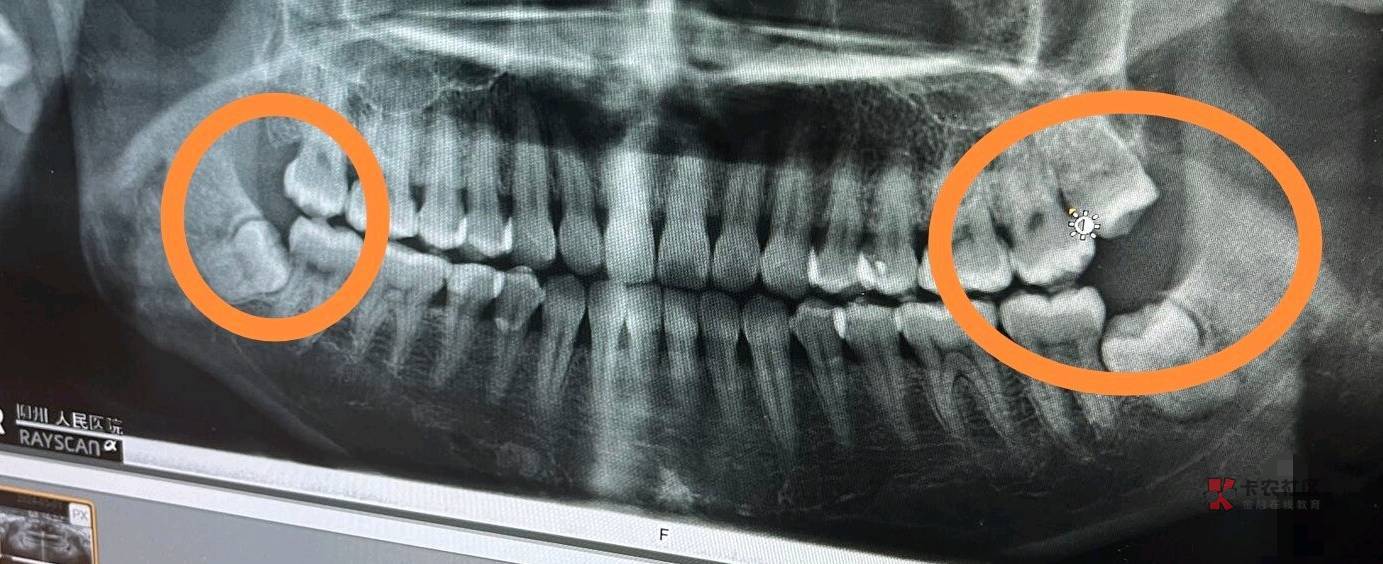

你这样的智齿不拔?到时候会把其他牙齿顶歪的,我之前400一颗的,前面没有拔,后面都被顶歪了,多花了一百拔掉的,这个好像可以报销吧

这个价格正常啊,可以去多家医院问下价格,不拔的话会把前面的顶烂的

智牙不拔 把旁边牙顶坏了

我的都长出来 把傍边和上面牙都整坏了